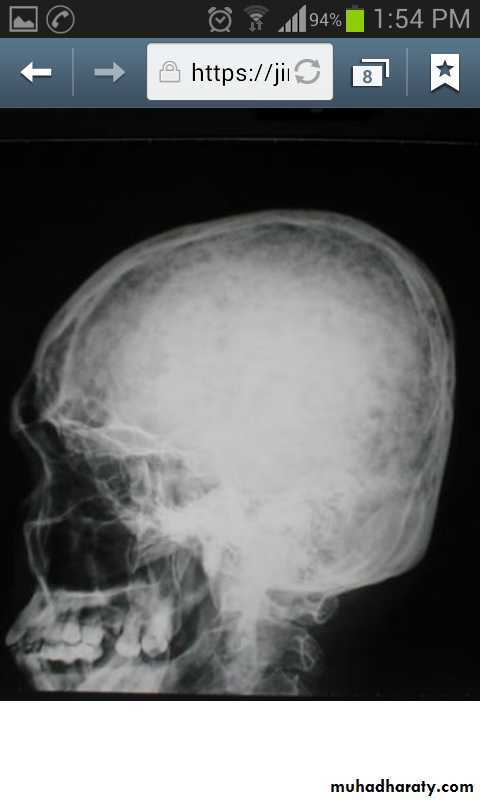

Skeletal X-rays:Normal in early disease

Demineralization

Subperiosteal erosions and terminal resorption of phalanges

Salt and paper appearance on lat. skull x-ray

Osteopenia and osteoporosis by DEXA